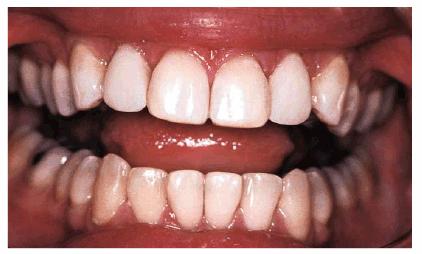

RESULT: By comparing occlusal views, one can see how effective the two

procedures were in creating the illusion of straightness (see Figures 24-3F, and 24-3G). A more proportional smile can be

seen by comparing Figures 24-3H, and 24-3I

Figure 24-3H: Pretreatment view of the smile.

Figure 24-3I: Post-treatment view showing better harmony with the smile.